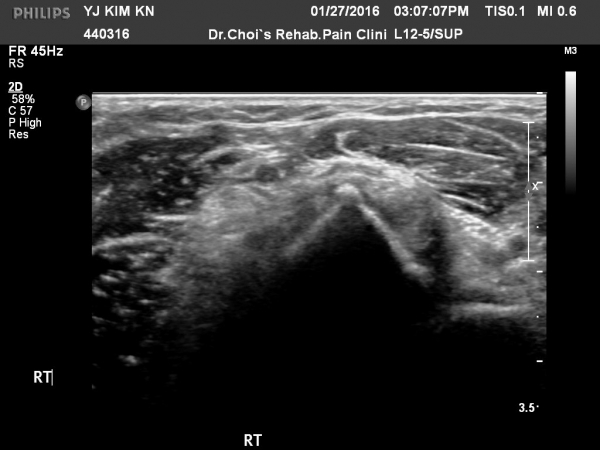

¿ìÃø ÆÈ²ÞÄ¡ ¾ÕÂÊ ÀÌµÎ¹Ú±Ù°Ç È¾´Ü¸é°Ë»ç¿¡¼­   ÀÌµÎ¹Ú±Ù°Ç ÁÖÀ§ ¼ö¾×Àú·ù¿Í ÀÌµÎ¹Ú±Ù°Ç ºÎÁ¾ÀÌ °üÂûµÊ(»çÁø 7, 8).

ÀÌµÎ¹Ú¹Ú±Ù°Ç ºÎÂøºÎ¿¡¼­ ¿ä°ñµ¹±â °ñ±Ø°ú ÀÌµÎ¹Ú±Ù°Ç Àú¿¡ÄÚ ºÎÁ¾ÀÌ °üÂûµÊ(»çÁø 9).

ÀÌµÎ¹Ú±Ù°Ç Á¾´Ü¸é°Ë»ç¿¡¼­ ¿ä°ñµ¹±â µ¹Ãâ, À̵ιڱٰÇÀÇ ºÎÁ¾ ¹× ¿¬°á¼º ¼Ò½ÇÀÌ °üÂûµÊ(»çÁø 10).